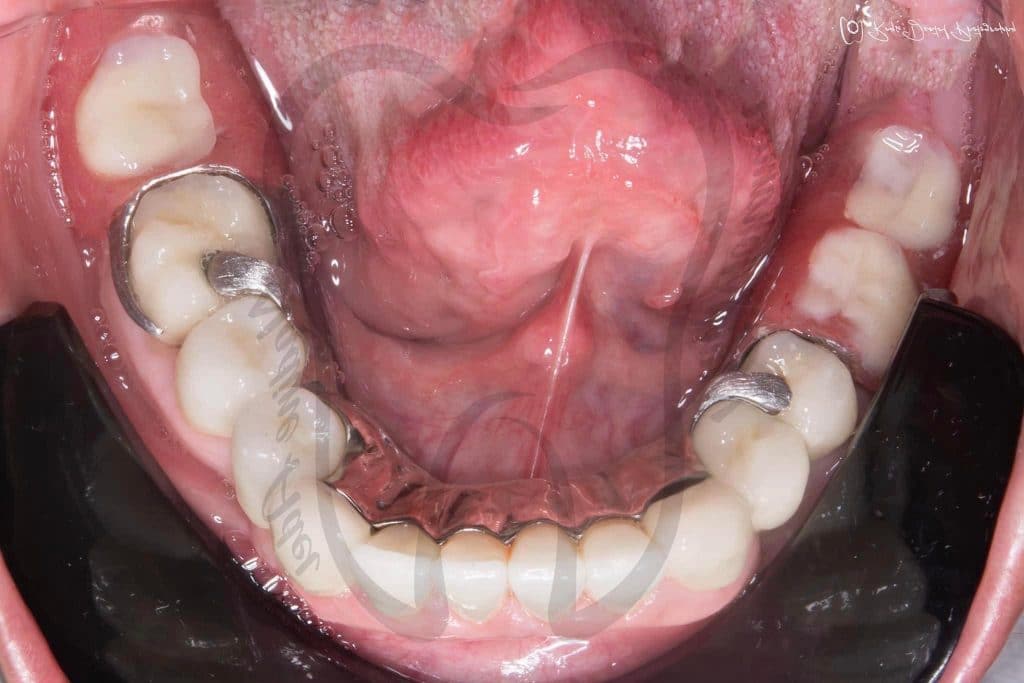

📌 Lower Arch Class I Metallic RPD